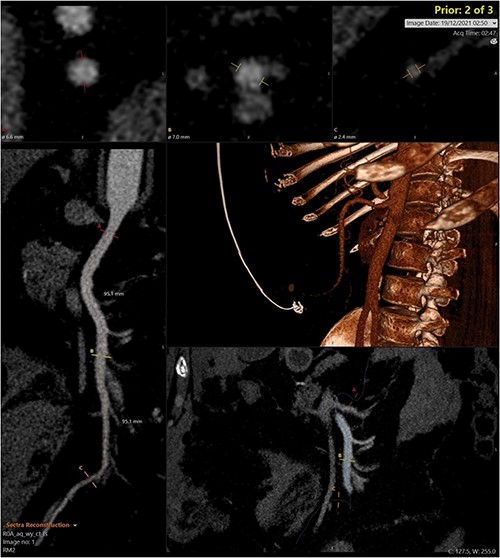

A CT abdomen-pelvis (CT-AP) revealed an acute haematoma inferolateral to the third part of the duodenum and another at the root of the mesentery. High density fluid related to the mesenteric bleed was also seen extending from the right para-colic gutter into the pelvis and in the peri-hepatic region. The patient was admitted under general surgery, stabilized with intra-venous fluid resuscitation, co-amoxiclav and metronidazole and cross matched for four units of blood. A CT-angiogram demonstrated acute haemorrhage throughout the abdomen with a 104 x 62 mm haematoma arising centrally at the level of L2 within the mesenteric fat (Fig. 1). The haematoma did not appear to originate from any specific mesenteric vessels but was related to some mid and distal jejunal loops. The angiogram also showed discontinuity when tracing the proximal and mid jejunal loops inferiorly, extensive haemorrhagic peritoneal fluid around the liver extending inferiorly (Fig. 2) and a small amount of peri-splenic haemorrhagic fluid. Curved reformatting of the angiogram revealed no abnormalities within the superior mesenteric artery (Fig. 3).

CT angiogram showing a large acute mesenteric haematoma. Figure 1 is taken from an axial section of the patient’s initial CT angiogram of the abdomen and pelvis. The arrow shown highlights an area of high-density fluid representing a 104 x 62 mm acute mesenteric haematoma.

Curved reprogramming of the initial CT angiogram. Curved reprogramming of the patient’s initial CT angiogram showed no evidence of an aneurysm within the superior mesenteric artery, effectively ruling this out as a cause of the patient’s acute bleed.